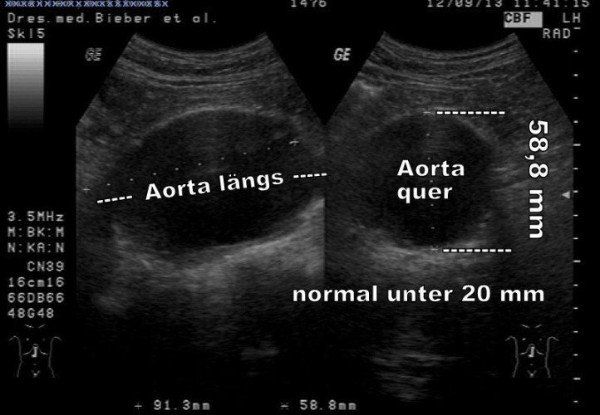

Beispiel für ein Aortenaneurysma

Trotz der enormen Größe der Erweiterung der Hauptschlagader hatte dieser damals 54 jährige (!) Patient keine Beschwerden, die auf dieses Risiko hindeuteten. Es war ein Zufallsbefund bei einer Untersuchung aus anderem Anlaß.

Nach weiterer Diagnostik konnte er erfolgreich und ohne Komplikationen operiert und damit geheilt werden.